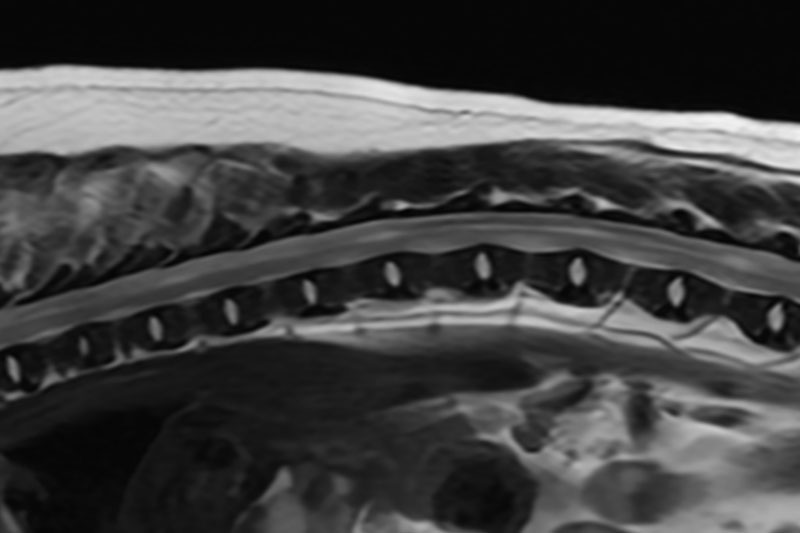

검사 전 최소 8시간 금식, 4시간 금수를 유지해 주세요.

현재 복용 중인 약물이나 보조제가 있다면 의료진에게 미리 알려 주세요.

심장질환, 신부전, 간질환 등 기저 질환이 있다면 반드시 사전에 말씀해 주세요.

이전에 마취 중 이상반응이 있었다면 꼭 알려 주세요.

검사 전 시행되는 마취 전 검사(채혈·X-ray·초음파 등)를 안내받고 준비해 주세요.

촬영을 위해 목걸이, 하네스, 의류, 금속성 액세서리를 모두 제거해 주세요.

검사 당일에는 흥분이나 스트레스를 최소화할 수 있도록 안정된 상태로 방문해 주세요.